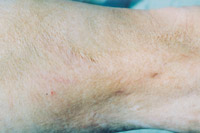

7.淺Ⅲ度創(chuàng)面(右大腿及膝關(guān)節(jié)外側(cè))自行愈合后3年,少量瘢痕平整柔軟,無增生,少量色素缺失,皮膚彈性好,不影響功能